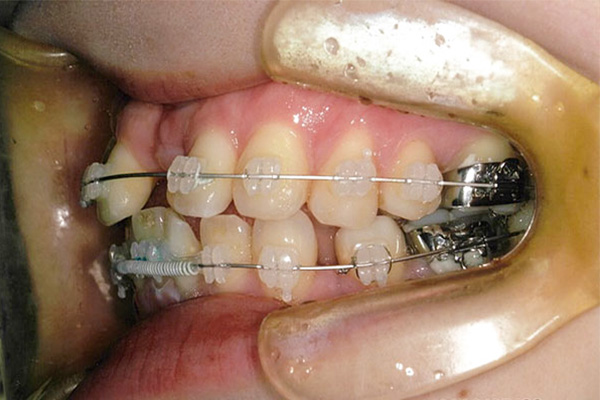

6ヶ月後